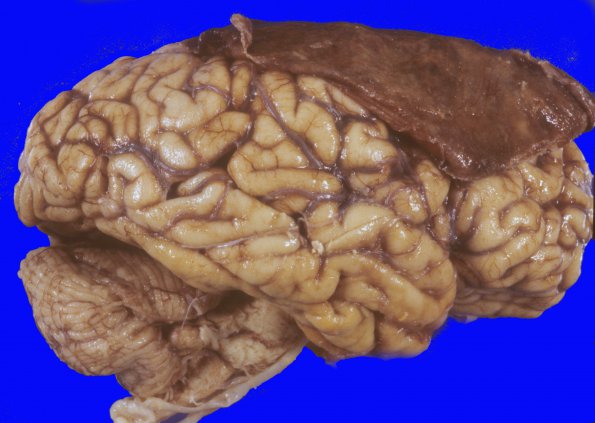

Cases 17A-D Multiple gross cases without histories. ---- 17A1,2 A subdural hemorrhage involving the right frontal and-parietal lobes